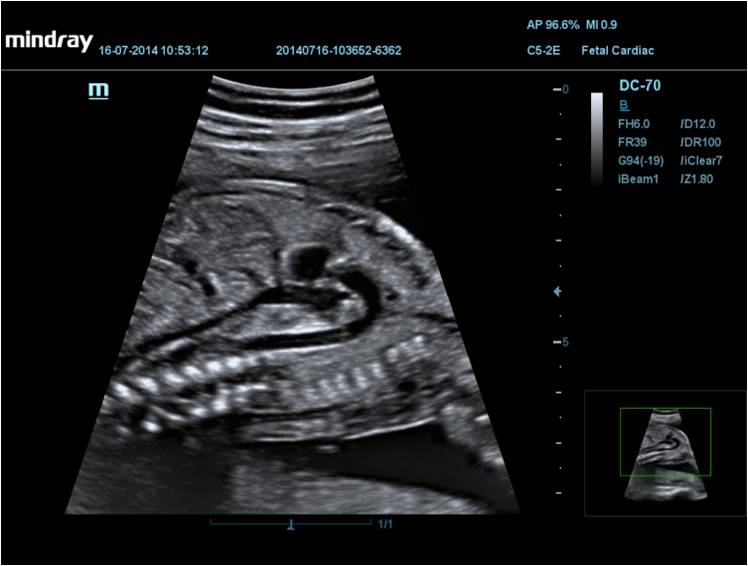

Mindray DC-70 Exp с технологией X-Insight – это узи-аппарат для высококачественной диагностики. Преимущества: высокая эффективность, точность визуализации, результат в «одно касание» с экспертными датчиками. Рекомендуется для государственных учреждений.